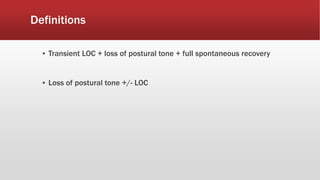

This document discusses various cases of collapse and syncope. It defines collapse as transient loss of consciousness with loss of postural tone and full recovery. Syncope is defined as loss of postural tone with or without loss of consciousness and full recovery. It then discusses the multiple potential causes of collapse and syncope including toxicological, cardiac conduction abnormalities, structural cardiac issues, autonomic dysfunction and more. It then goes through 9 case examples, discussing important questions to ask, potential tests and interventions for each case.